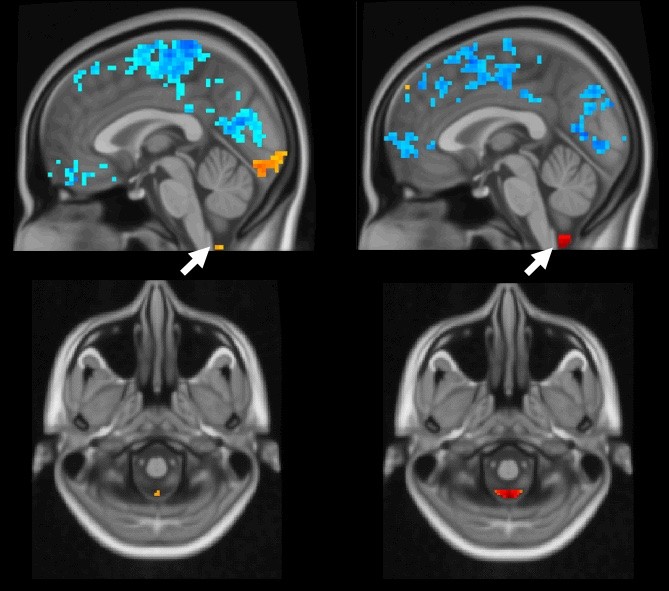

Nel cervello umano, in presenza di attività (blu), il fluido spinale cerebrale si muove (arancione e rosso). A sinistra si vede un accoppiamento più debole che indica l'Alzheimer, a destra un accoppiamento sano (Fonte: Xiao Liu)

Usando dati della risonanza magnetica funzionale (fMRI), gli scienziati hanno scoperto che l'attività cerebrale si accoppia al movimento del fluido cerebrospinale negli esseri umani. La fMRI misura l'attività cerebrale di una persona in modo non invasivo, da un segnale dipendente dal livello di ossigeno del sangue (BOLD, blood oxygen level-dependent); il sangue si sposta nella parte attiva del cervello, illuminandosi mentre si muove. Negli individui sani, una volta che il segnale BOLD lampeggia globalmente in tutto il cervello, il fluido cerebrospinale fluisce dalla base del cervello in rapida successione.

"Più debole è l'abbinamento tra segnale globale BOLD e flusso del fluido cerebrospinale, maggiore è il rischio di MA", ha dichiarato Xiao Liu, assistente professore nel Dipartimento di Ingegneria Biomedica e nell'Institute of Computational and Data Sciences, che ha guidato lo studio. "Questo potrebbe essere un potenziale marcatore di scansione per le malattie neurodegenerative, nonché un approccio di valutazione non invasivo per il sistema glinfatico scoperto di recente, che aiuta il cervello a disfarsi delle tossine".